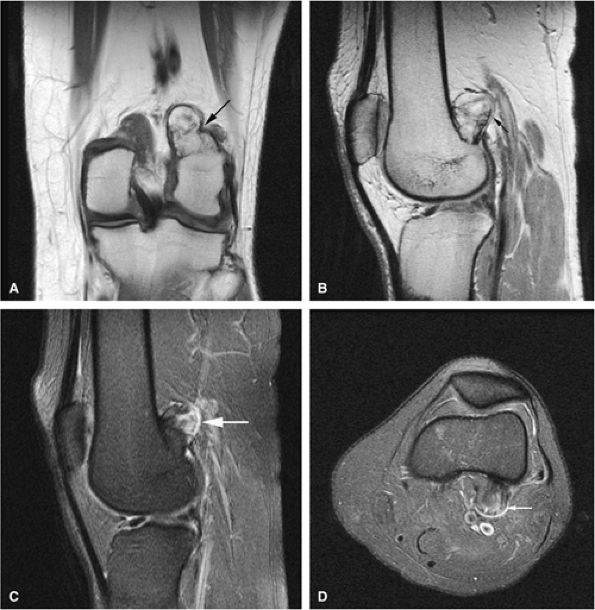

FIGURE 14-28 ● A small osteochondroma arising from the proximal fibula (arrows) is demonstrated on an anteroposterior radiograph (A), a sagittal proton density-weighted image (B), and axial T1-weighted (C) and fat-suppressed T2-weighted fast spin-echo (D) images of the knee.